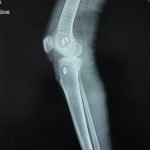

Orthopaedic Surgeon | Arthroscopy & Joint Replacement Specialist

- Robotic Joint Replacement

- Knee Replacement Surgery